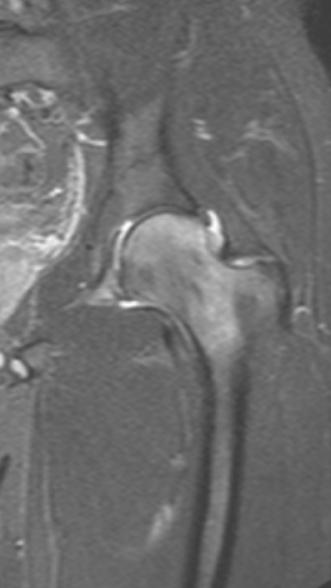

Асептический некроз тазобедренного сустава

3 процедуры ФДТ, 9 процедур MBST, 20 процедур ИПМТ

Параметры изменяются в зависимости от процедуры

Дата публикации: 22.08.2025 14:26:45